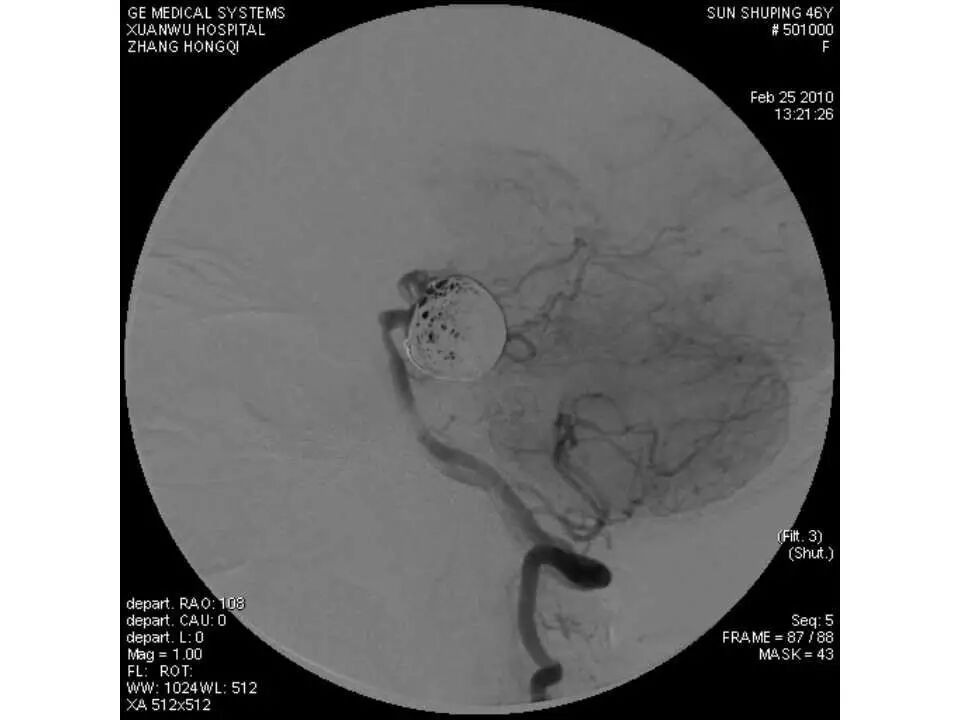

今天为大家分享的是“强生医疗CNV-神经介入专栏”第十五期,由首都医科大学宣武医院何川教授带来的“颅内动脉瘤介入治疗”精彩讲课视频及PPT,欢迎观看、阅读。文章仅代表作者个人观点,如有不同见解,欢迎同道斧正!

何川 ,首都医科大学宣武医院副主任医师,中国医师协会神经介入专业委员会常务委员,长期从事脑血管病和脊髓血管病的手术及介入治疗和相关研究工作。首都医科大学神经外科博士,师从于中国神经介入开创人凌锋教授;日本东北大学医院脑血管病治疗科博士后,师从于日本国脑血管病血管内治疗的开创者高桥教授。